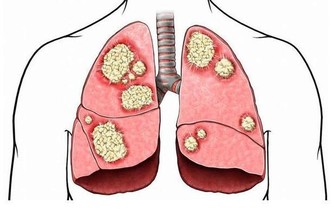

5、懶得體檢

談到體檢,有的人會想:體檢多費錢啊,不去!有的人則會認為自己身體很好,並不需要。

但事實是,不少潛伏在人體的疾病,不通過體檢很難發現。如一些患有隱匿性心髒病的人,日常生活中並沒有什麼症狀,可一旦發作,後果不堪設想。

★建議:每年至少體檢一次,檢查的重點項目是心、肺、肝、膽、胃等重要器官,以及血壓、血糖等重要指標。